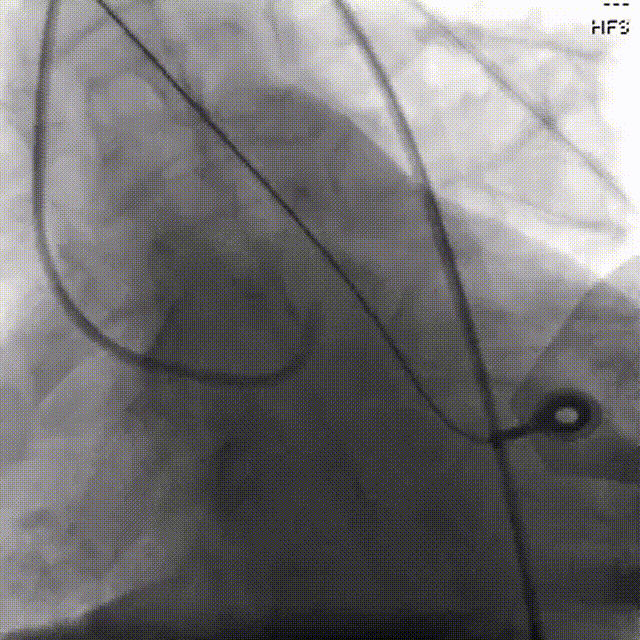

抽吸【例】量|抽吸新主【张】再论规范化操作